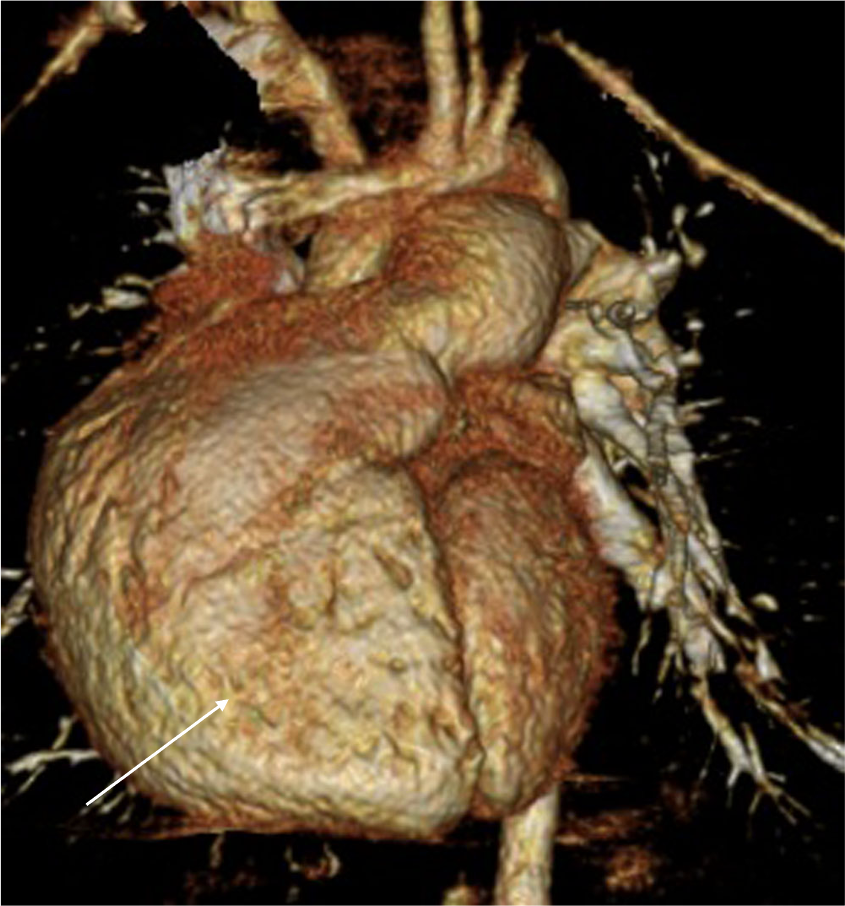

3歳、 男児、 9kg、 心房中隔欠損

染色体異常が判明している男児。肺炎で入院した際のレントゲンで右心系の拡大を指摘された。心臓超音波検査にて心房間の短絡が疑われた。心房中隔欠損症疑いの精査、肺静脈還流異常の除外目的で造影CT検査が施行された。

心房中隔欠損症は左右の心房に短絡を生じる先天性の病態である。欠損部位により、二次孔欠損、一次孔欠損および冠静脈洞欠損に大別される。まず身体所見、胸部レントゲン写真および心電図検査が行われ、解剖学的構造を評価するために、心エコー検査が施行される。心エコー検査で十分な情報が得られない場合、欠損孔の部位や形態を評価するために造影CTが施行される。最終的な治療方針の決定にはカテーテル検査が施行されることが多いが、あらかじめ病変の形態や解剖を把握するために造影CTは有用である。また肺静脈還流異常を合併することがあるため、その有無を評価することができる。短絡が小さいものについては経過観察が可能であるが、ある程度大きい病変に対しては治療が必要となる。治療はカテーテルによる閉鎖術、外科手術が挙げられる。カテーテルによる閉鎖術が選択される場合には、造影CTは治療計画用にも用いられる。その場合には、任意多断面再構成(MPR)やvolume rendering(VR)像などを活用する。